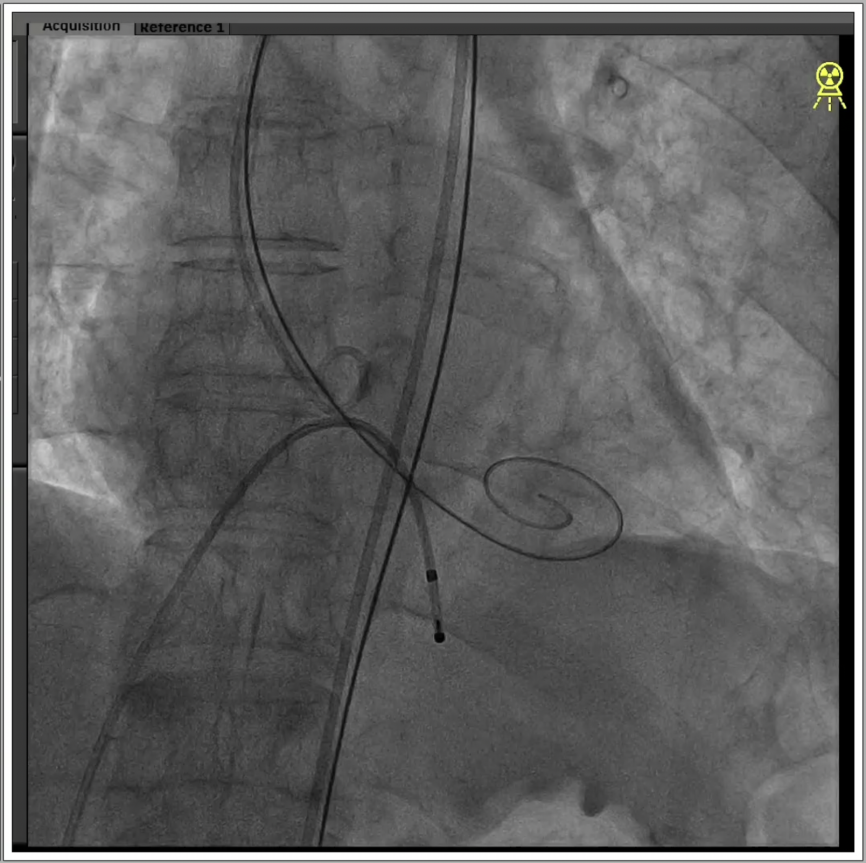

6、瓣膜植入且撤出导丝后,造影超声结果均显示瓣膜工作良好,术后导管测量压差8mmHg,经胸超声检测微量瓣周漏,手术成功。

7、边退鞘边“冒烟’排除主入路并发症,进行血管缝合,手术顺利结束。